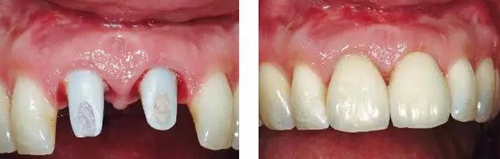

圖14、最終修復(fù)體就位,冠頸部較窄。沒有任何牙齦和牙齦乳頭的退縮。

圖15、種植體植入后12個(gè)月的微笑相。